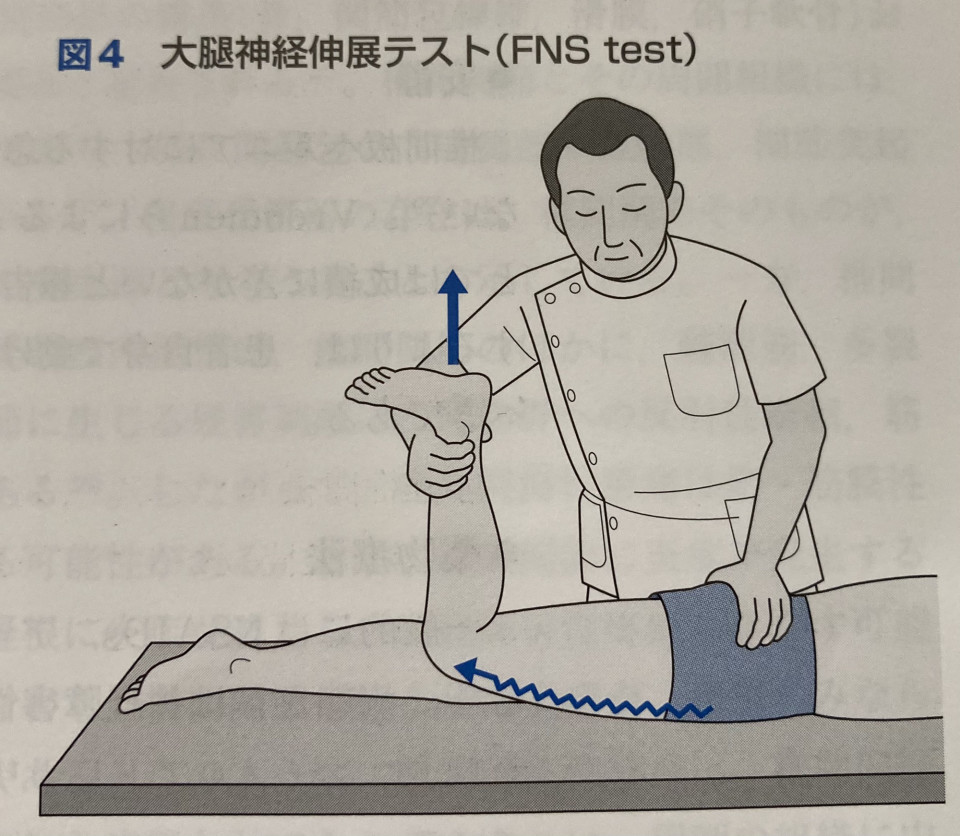

坐骨神経痛のお隣さんは大腿神経痛です。

坐骨神経は有名ですが大腿神経というのは一般だとあまり聞きません。

坐骨神経に対する各テストを行います。

SLRという坐骨神経を伸張させて痛みを誘発させるテストを行いました。

右は陰性、左は陽性でした。

つまり右の神経は問題なく、左の神経は圧迫されて神経に何らかのトラブルがあると考えられます。

坐骨神経はL4〜S3レベルで狭窄を受けると症状が出ます。

どこで狭窄を受けているが問題になります。

それは脊柱管(背骨の中の神経)、神経根(神経が左右に分かれて出る出口)なのか、神経の近くを通る筋肉の影響なのか、姿勢などの問題で神経が圧迫されるのか確認する必要があります。

それぞれの箇所で神経を一時的に圧迫から解放するテストを行いどこが原因なのか判断していきます。